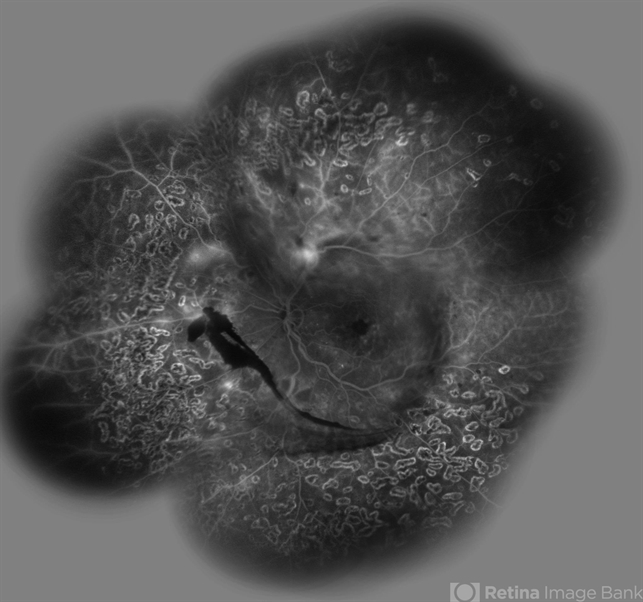

- retinal neovascularization, preretinal hemorrhage, scatter laser photocoagulation

- Hamid Ahmadieh, MD, Ophthalmic Research Center, Labbafinejad Medical Center, Shahid Beheshti University of Medical Sciences

- Heidelberg HRA

- Wide- field FA image of a 55-year-old woman with active PDR and the history of scatter laser photocoagulation.